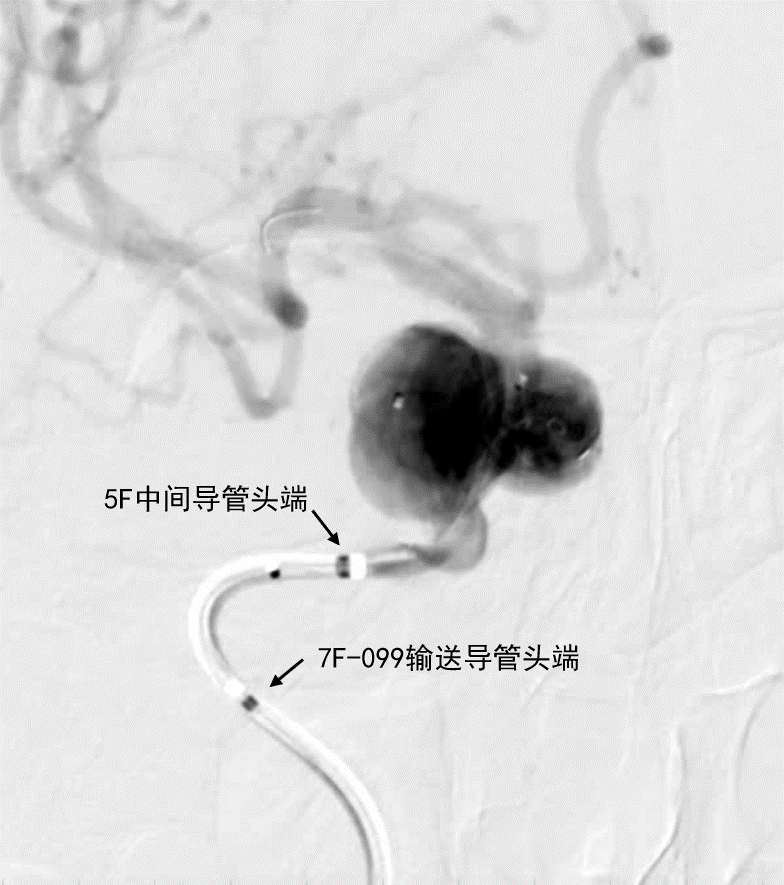

- 新路图下,沿微导管依次填入数枚弹簧圈,将动脉瘤填塞。复查造影证实动脉瘤达完全栓塞,载瘤动脉通畅。

动脉长鞘怎么置入深谋远路 | 千人皆翘首,万唤今始来——国内首款7F长鞘在血流导向密网支架联合弹簧圈栓塞治疗动脉瘤的首次应用_https://www.jmylbn.com_新闻资讯_第27张术后正位造影

术后侧位造影

深瑞达7F输送导管,中间导管和弹簧圈微导管的位置关系